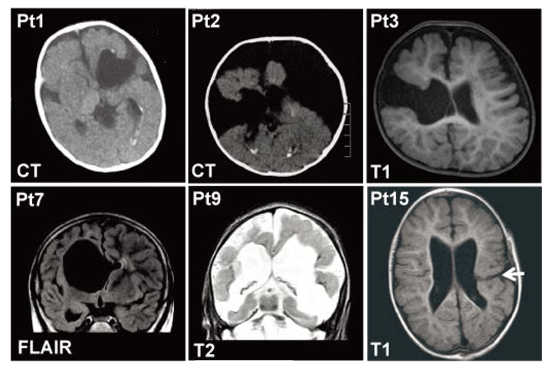

変異を有する患者の頭部MRI画像では、片側性あるいは両側性の孔脳症や裂脳症が認められ、その程度も様々でした(図1)。石灰化を伴うようなTORCH症候群1)を疑う症例においてもCOL4A1 変異が関与していることが分かりました(図1)。また、脳での異常(孔脳症・裂脳症)以外にも、目や筋肉の異常および溶血性貧血など幅広い表現型を引き起こすことが明らかとなりました(表1)。

<図1> COL4A1 変異を有する患者の脳画像。患者1(Pt1)および患者2のCT画像では、側脳室周囲の石灰化を認め、TORCH症候群が疑われた。患者3, 9, 15(矢印)はそれぞれ裂脳症を呈している。患者7では片側の孔脳症を認めた。